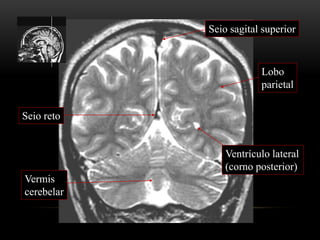

Seio sagital superior

Ventrículo lateral

(corno posterior)

Lobo parietal

Cerebelo

Vermis

Tenda do